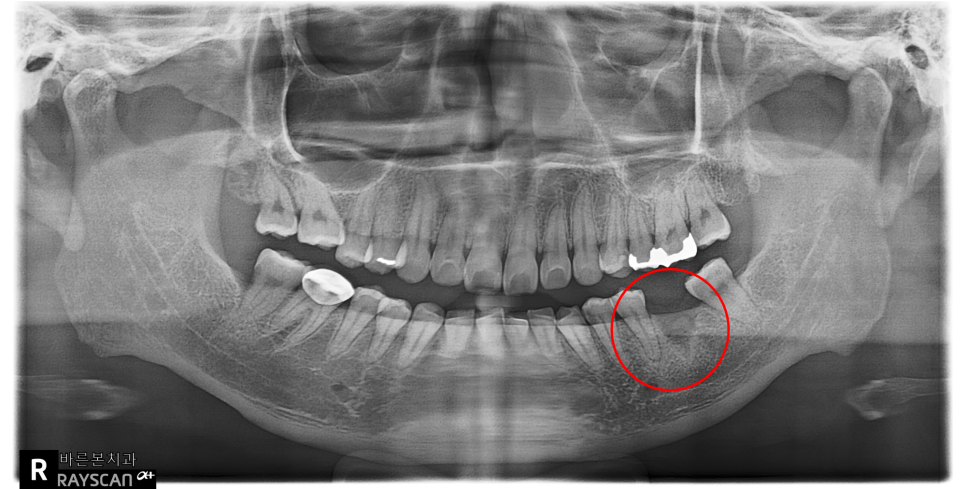

세류동치과에서 촬영한 x-ray 사진입니다.

빨강색동그라미가 수년전 타치과에서

치료를 받았던 임플란트입니다.

잇몸뼈에 식립된 어금니임플란트 주변으로

염증이 심하게 보이네요.